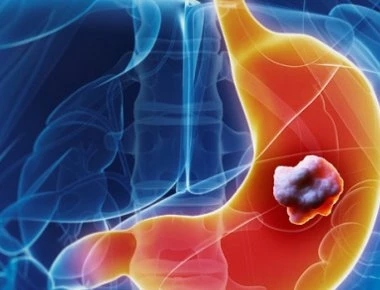

Πολλοί αγνοούν σαν «κάτι περαστικό» αυτά τα πρώιμα συμπτώματα καρκίνου του στομάχου!

Ο καρκίνος του στομάχου είναι συνήθως ευκολότερο να θεραπευτεί, εάν έχει διαγνωστεί νωρίς. Ο καρκίνος του στομάχου είναι ένας όγκος που σχηματίζεται όταν τα κύτταρα του στομάχου σας αναπτύσσονται με μ...